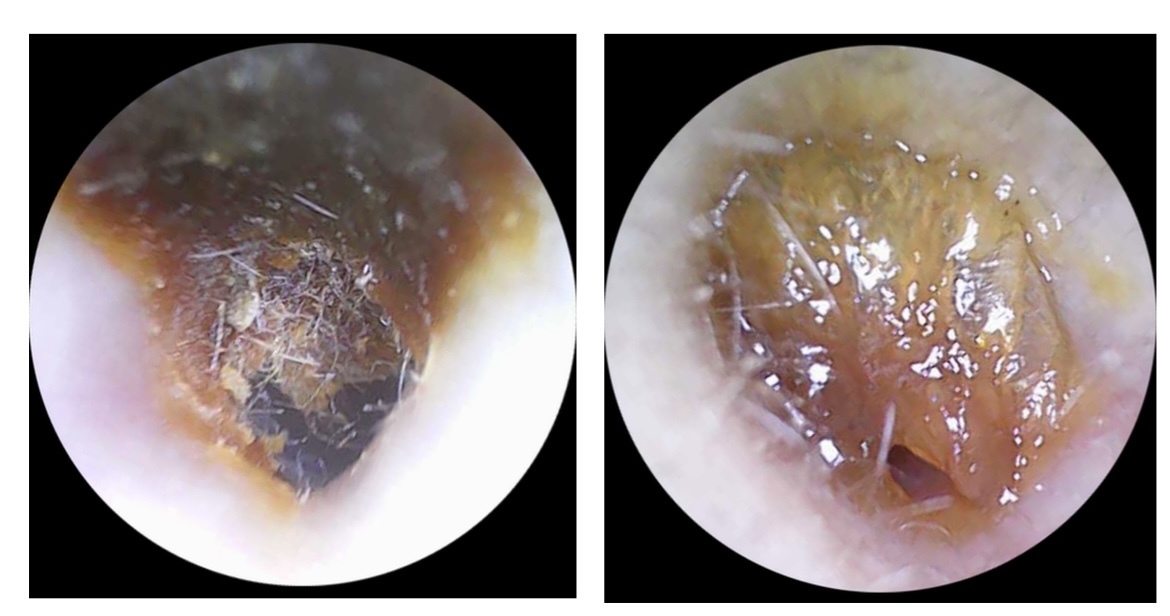

Самое частое, что мы видим:

Серные пробки ( можем удалить на приеме или назначить капли для растворения серы домой)